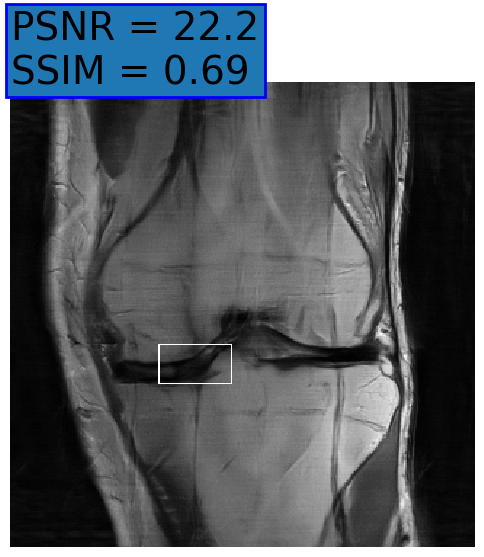

Figure 6: Examples of reconstruction results. Rows 1, 3, and 5: The reference (GT) fully sampled image, the reconstructed images obtained by the three models (1-3), NPB-REC, baseline, E2E-VarNet trained with Dropout, and the Std. map derived from our method for example from the knee dataset, the brain dataset, and the brain dataset sampled with radial mask L=50𝐿50L=50italic_L = 50, respectively. Rows 2, 4, and 6: The corresponding annotated ROIs of the cartilage, edema, and nonspecific white matter lesion respectively.

Fig. 6 depicts the reconstruction results obtained by (1) our NPB-REC approach, (2) the baseline, and (3) Monte Carlo Dropout, for examples of both the knee (row 1) and the brain (rows 3 and 5) datasets. The first two examples were obtained by the models that trained on brain data and were tested on knee data (row 1) and vice versa (row 3). In knee images, all three models exhibit minimal differences in handling pronounced folding artifacts. However, our approach demonstrates superior reconstruction performance for anatomical annotations or pathological regions, labeled by radiologists, in terms of both PSNR and SSIM. The last example is a reconstructed brain image that was obtained by the three models, where the k-space input is undersampled by a radial mask with L=50𝐿50L=50italic_L = 50. Table 2 presents the mean PSNR and SSIM metrics, calculated over the whole inference knee dataset, for the three models that were trained on brain data. The NPB-REC method shows a considerable improvement in the generalization ability on knee data for higher acceleration rates R=8𝑅8R=8italic_R = 8 and R=12𝑅12R=12italic_R = 12 in both annotation regions and the whole images. However, both the baseline and Dropout methods show a slight improvement in the metrics in the case of a small acceleration rate R=4𝑅4R=4italic_R = 4. Table 3 shows the results of the inverse experiment, i.e. calculating the mean PSNR and SSIM metrics over the whole brain inference set for the three models that were trained on knee data only. The generalization capability of the three models in the case of an anatomical distribution shift from the knee to the brain is better than the opposite scenario. This is not only measured quantitatively by the SSIM and PSNR metrics, but also visible in the predicted reconstructions. For instance, the brain MRI reconstructed images exhibit fewer artifacts than the produced knee images, as shown in row 1 vs. row 3 in Fig. 6.

Table 3 presents the mean PSNR and SSIM metrics calculated over the whole inference knee dataset that were obtained by the three models, where the k-space input is undersampled by a radial mask with L=50𝐿50L=50italic_L = 50 and L=40𝐿40L=40italic_L = 40. Although the NPB-REC approach improves the accuracy of reconstruction when the metrics are measured on the whole image, it doesn’t yield the best performance on the annotation ROIs. However, it is still able to reconstruct high-quality images while preserving the important anatomical content in these annotations. This can be clearly observed in the last row in Fig. 6, where the topmost part of the ROI image predicted by NPB-REC is preserved, in contrast to the other benchmarks.